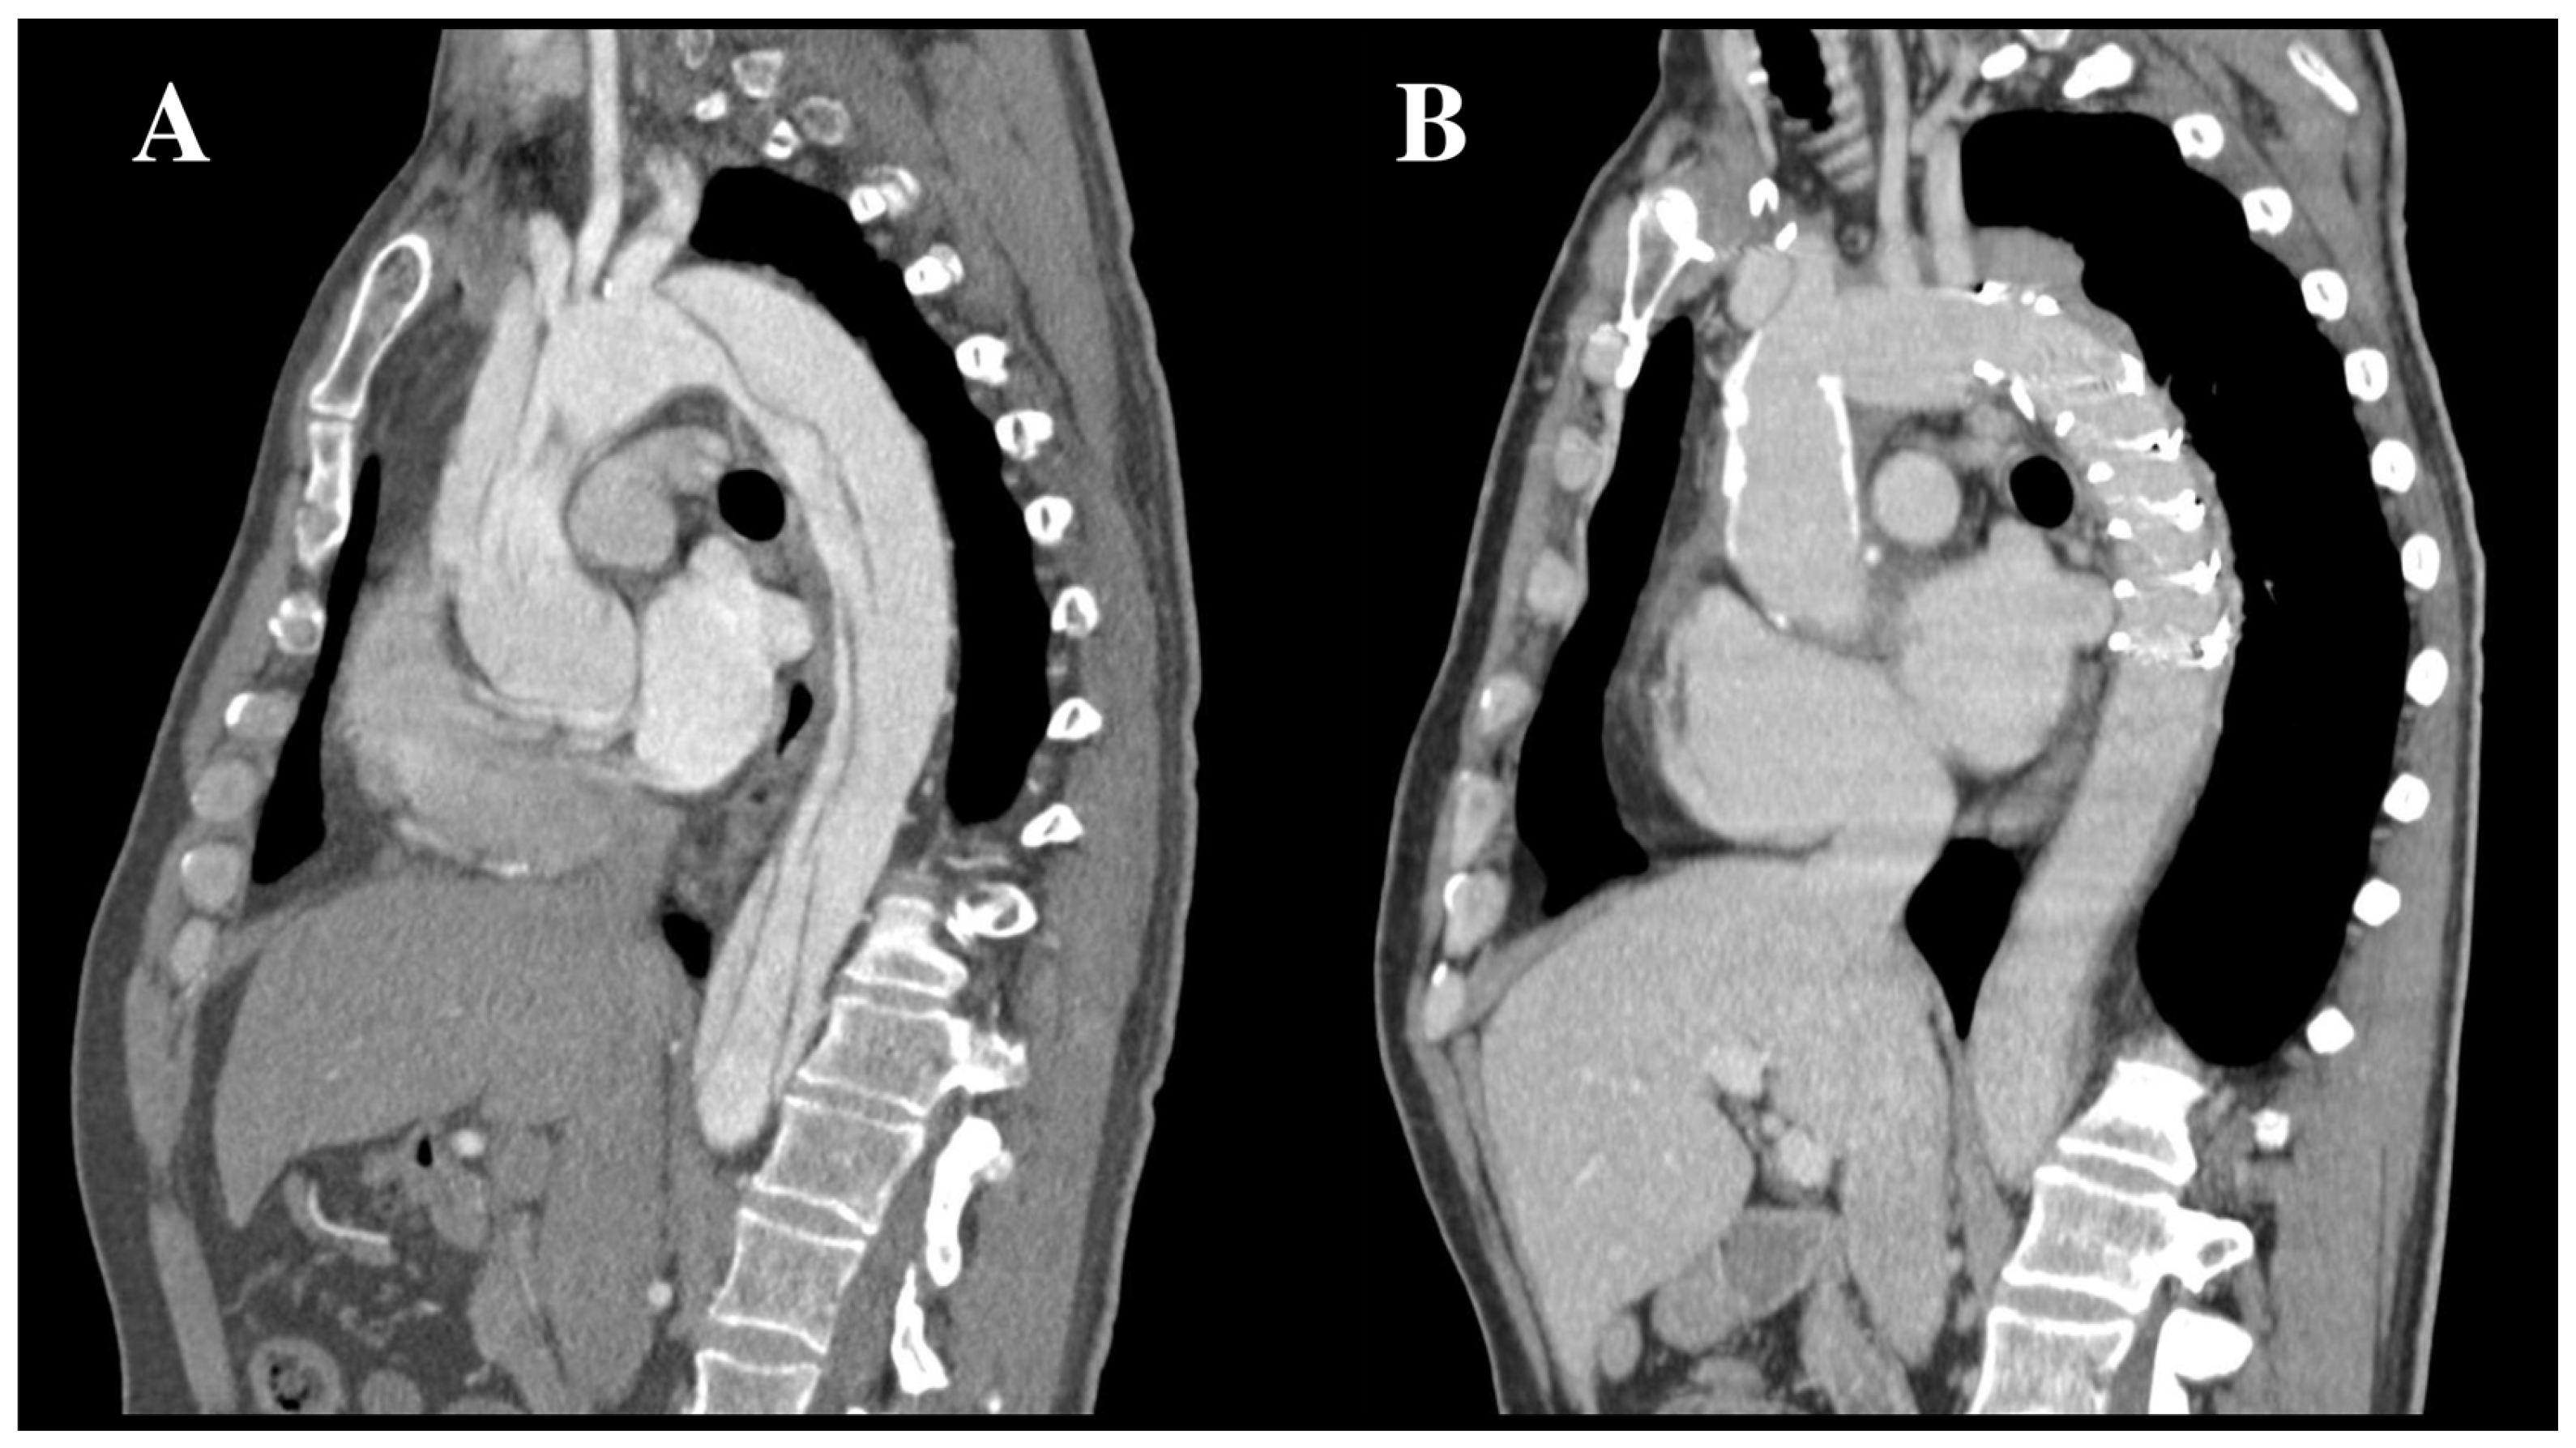

2. FET Technique: General Considerations

3.2. Chronic Aortic Dissection